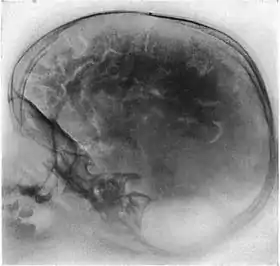

تصوير الدماغ المحقون بالغاز

تصوير الدماغ المحقون بالغاز[1] أو تصوير الدماغ الغازي[1] (بالإنجليزية: Pneumoencephalography) ويُعرف اختصارًا PEG، هو إجراء طبي كان شائعاً، حيثُ يُسحب فيه مُعظم السائل الدماغي الشوكي من حول الدماغ، عن طريق بزل قطني ويستبدل بالهواء أو الأكسجين أو الهيليوم، وذلك لجعل ظهور هياكل الدماغ أكثر وضوحًا في صورة الأشعة السينية. اشتُقَ من الطريقة البدائية في تصوير البُطينات، حيثُ كان يُحقن الهواء من خلال فُتحات محفورة في الجمجمة.

أُدخلَ هذا الإجراء في عام 1919 على يد جراح الأعصاب الأمريكي والتر داندي،[2] وأُجريَ على نطاقٍ واسع حتى أواخر السبعينيات، عندما استُبدلَ بتقنيات تصوير عصبي حديثة أكثر تعقيدًا وأقل رضاً.